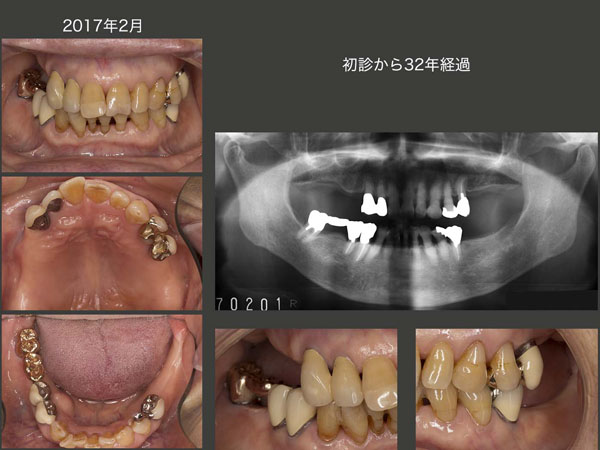

体調を崩し,通院が片道2時間以上かかる当院まで通うことが困難になり,2000年12月のリコールを最後に通院が途絶えた.連絡は年賀状だけであったが,17年2月,久しぶりにみせていただいた.しかし,驚いたことに,根面板を装着した左上7の近心頰側根を失った以外,この17年間何も問題が生じていなかった.パノラマX線写真をみると食事は左側の小臼歯部が中心になると思われる.左上5および左下5が無髄歯であるから,通常これらの歯に歯根破折が生じやすい.咬合力を上手く調節して咀嚼している,上顎に義歯が入っている右側でも結構咀嚼している等が考えられるが,これらの歯を連結固定したことも歯根破折の予防に繋がったのではないかと考えている.

上顎義歯に関しては,人工歯の形態を若干調整した.しかし,レストの適合,義歯床内面の適合等まったく問題がなかった.右下の残存歯が挻出し,右上の顎堤が吸収することはよく見受けられるが,この症例に至ってはまったくそのような所見はみられなかった.右下をブリッジにしたことで挻出しにくかった,あるいはなんだかんだ言って右側では,ほとんど咀嚼しなかったなど考えられる.私は後者ではないかと思っているが,よくまだ分からない.